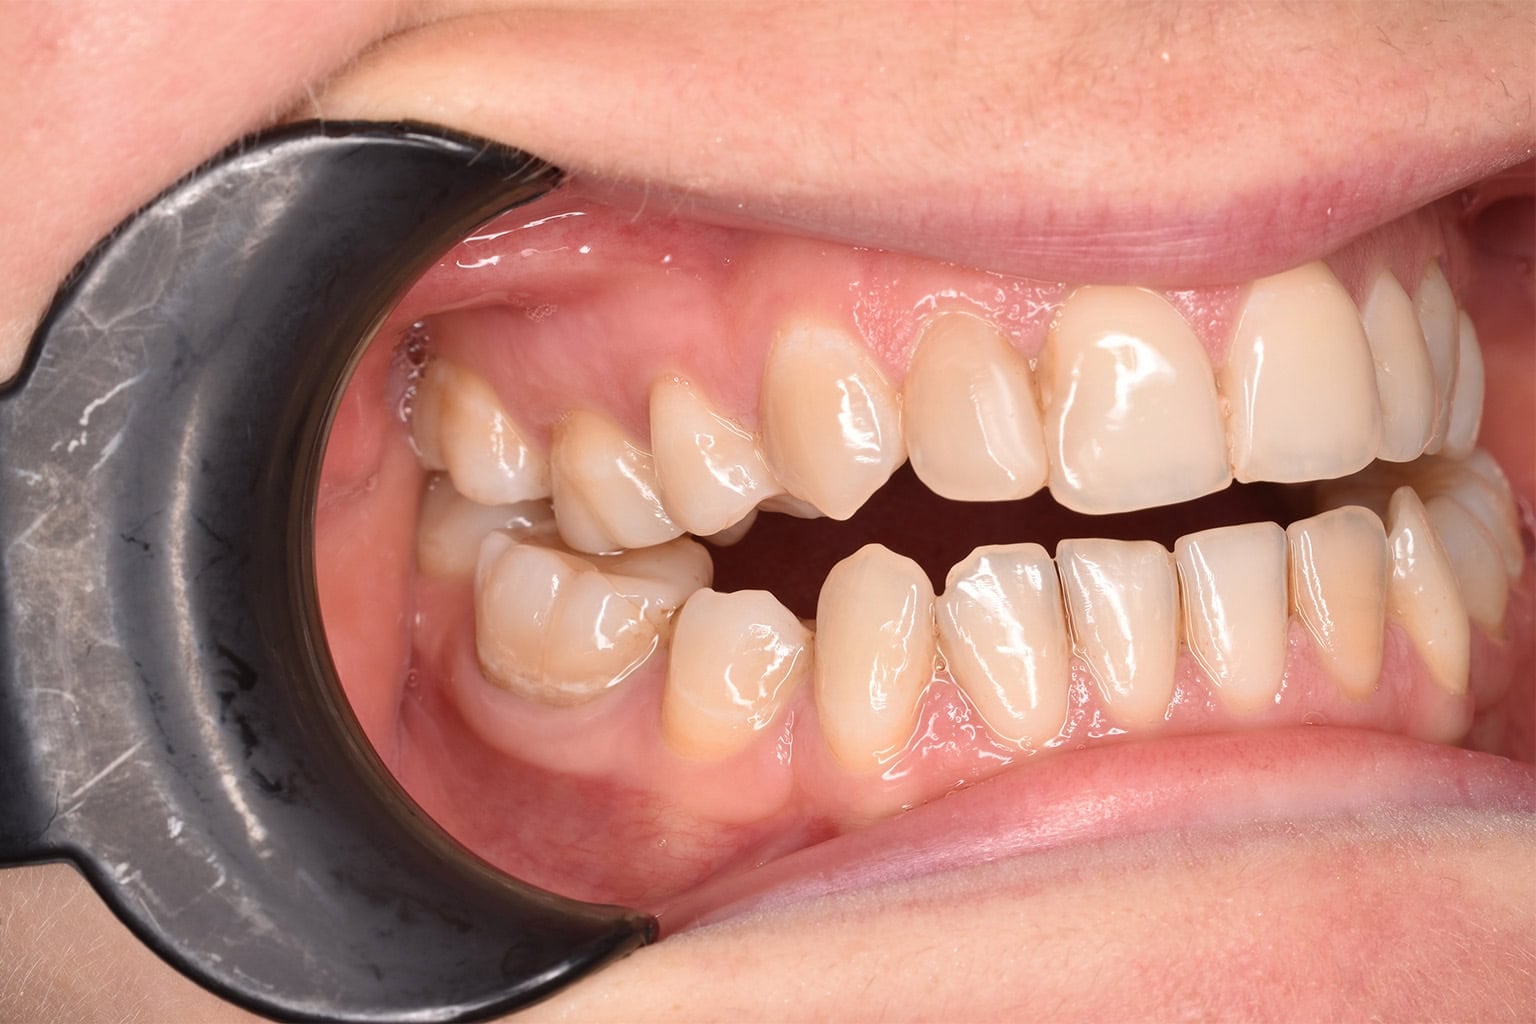

Vorher-Nachher-Ergebnisse

Echte Ergebnisse. Echte Menschen.

Jede Behandlung bei TIEFBLAU Kieferorthopädie ist so individuell wie der Mensch dahinter. In unserer Vorher-Nachher-Galerie zeigen wir Ihnen echte Behandlungsergebnisse aus unserer Praxis in der Kölner Südstadt: Schonend erzielt, präzise geplant und mit dem Anspruch, den wir seit über 40 Jahren an jede Behandlung stellen.

Die Bilder geben Ihnen einen Eindruck davon, was moderne Kieferorthopädie leisten kann, ob bei Kindern, Jugendlichen oder Erwachsenen.

Der sichtbare Unterschied

Dokumentiert. Überzeugend. Nachhaltig.